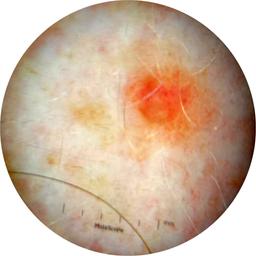

ISIC_3176953

Information

2135 x 2135

Clinical

Field Value

acquisition_day 410

age_approx 40

anatom_site_1 Head and neck

anatom_site_general head/neck

concomitant_biopsy False

diagnosis_1 Malignant

diagnosis_2 Malignant adnexal epithelial proliferations - Follicular

diagnosis_3 Basal cell carcinoma

diagnosis_confirm_type single image expert consensus

family_hx_mm False

fitzpatrick_skin_type I

image_manipulation instrument only

image_type dermoscopic

lesion_id IL_4059380

patient_id IP_8700330

personal_hx_mm True

sex female